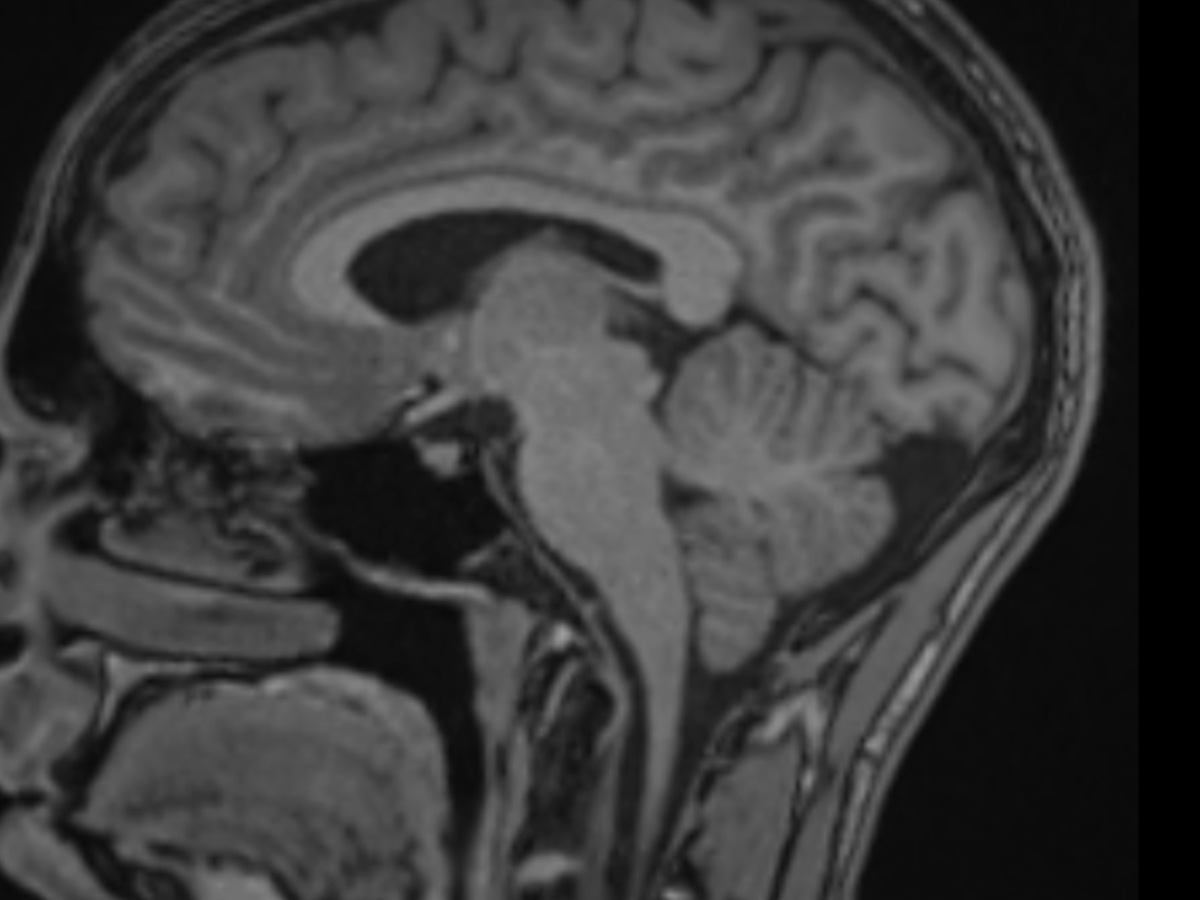

Después de consultar con varios especialistas, encontré a un neurocirujano experimentado que ha identificado no solo el quiste aracnoideo, sino también una malformación de Chiari: un descenso de las amígdalas cerebelosas por el canal espinal.

El quiste aparece como el saco oscuro detrás del cerebelo en la primera imagen y como el saco blanco en la segunda. Se aprecia también el descenso de las amígdalas cerebelosas a lo largo del canal espinal.

After consulting with several specialists, I found an experienced neurosurgeon who identified not only the arachnoid cyst but also a Chiari malformation: a prolapse of the cerebellar tonsils into the spinal canal.